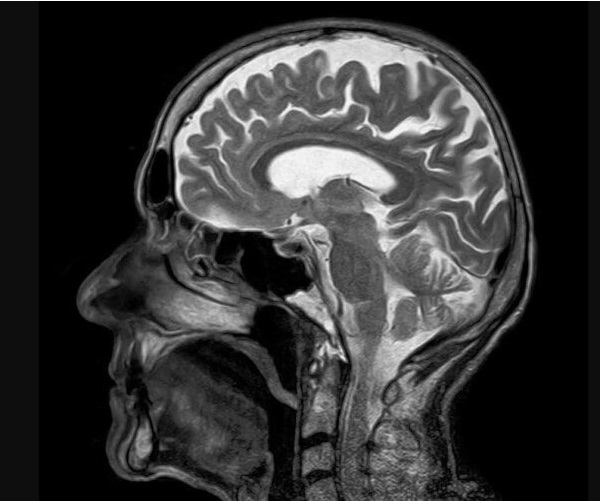

Razmere, ki prizadenejo živčni sistem – kot so možganske kapi, migrene in demenca – so prehitele bolezni srca in postale glavni vzrok za slabo zdravje po vsem svetu, je v petek pokazala velika nova analiza.

Vodilni avtor študije Jaimie Steinmetz iz IHME je dejal, da rezultati kažejo, da so bolezni živčnega sistema zdaj "glavni svetovni vzrok za celotno breme bolezni".

Raziskovalci so preuči, kako 37 različnih nevroloških stanj vpliva na slabo zdravje, invalidnost in prezgodnjo smrt v 204 državah in ozemljih od leta 1990 do 2021.

Možganska kap, ki je prej veljala za bolezen srca, je bila daleč najhujše analizirano nevrološko stanje, kar je povzročilo izgubo 160 milijonov let zdravega življenja.

Spremljala ga je oblika poškodbe možganov, imenovana neonatalna encefalopatija, migrene, demenca, vključno z Alzheimerjevo boleznijo, poškodbe živcev zaradi sladkorne bolezni, meningitis in epilepsija.